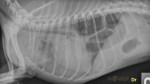

latérale droite